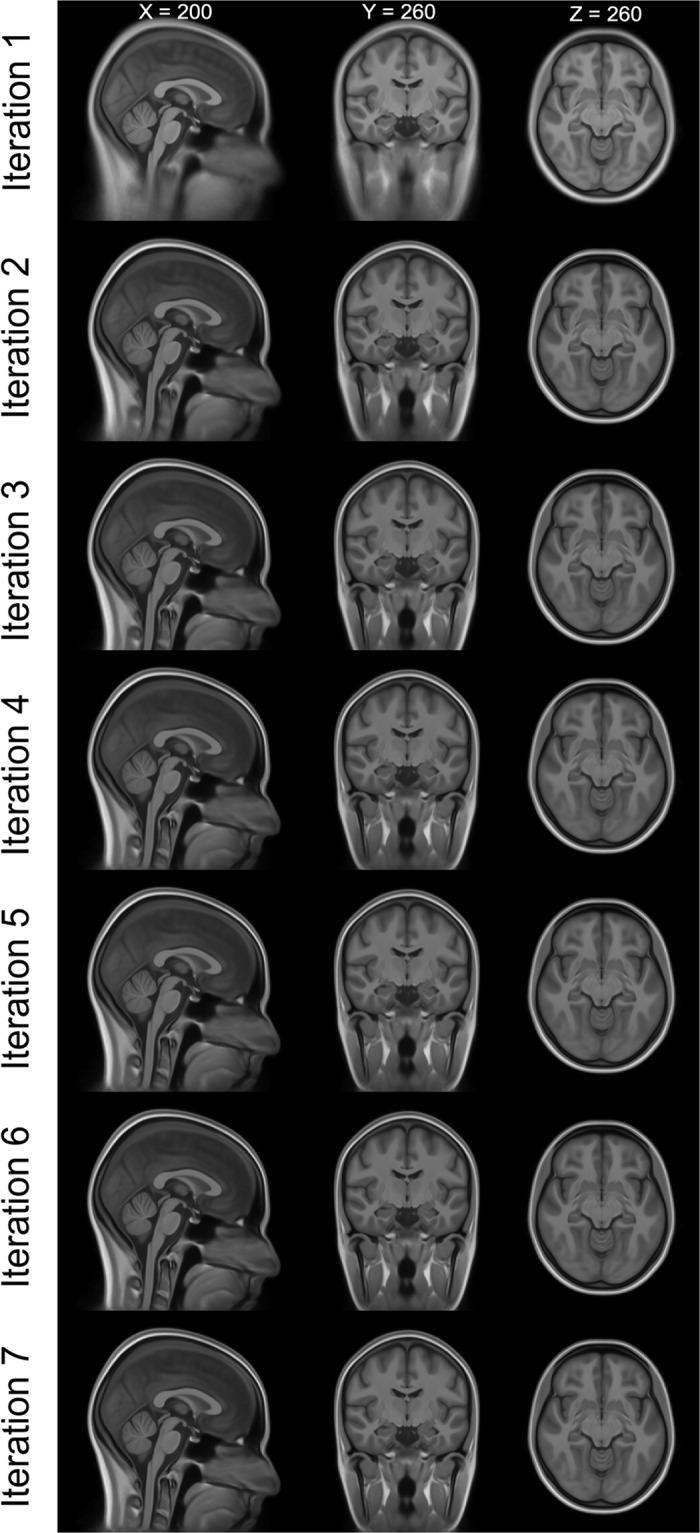

Big Field of View MRI T1w and FLAIR Template - NMRI225.

Image templates are a common tool for neuroscience research. Often, they are used for spatial normalization of magnetic resonance imaging (MRI) data, which is a necessary procedure for analyzing brain morphology and function via voxel-based analysis. This allows the researcher to reduce individual shape differences across images and make inferences across multiple subjects. Many templates have a small field-of-view typically focussed on the brain, limiting the use for applications requiring detailed information about other extra-cranial structures in the head and neck area. However, there are several applications where such information is important, for example source reconstruction of electroencephalography (EEG) and/or magnetoencephalography (MEG). We have constructed a new template based on 225 T1w and FLAIR images with a big field-of-view that can serve both as target for across subject spatial normalization as well as a basis to build high-resolution head models. This template is based on and iteratively re-registered to the MNI152 space to provide maximal compatibility with the most commonly used brain MRI template.